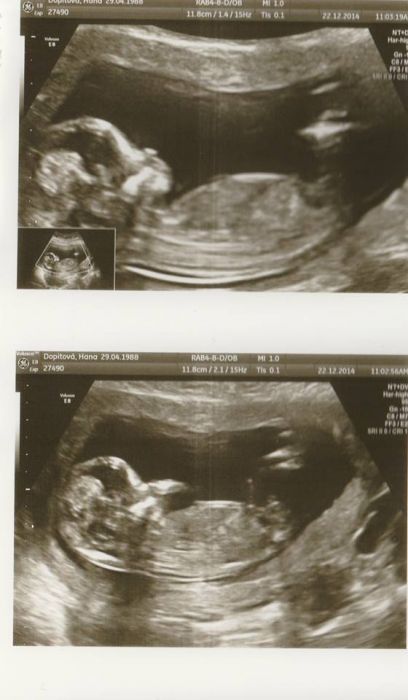

Přikládám fotečku ze screeningu, je to nakopírované tak kvalita nic moc, a pak ještě přikládám foto dárečků jak jsme to měli připravené pro rodinu. Všechny jsme objeli 23. a radost všude veliká